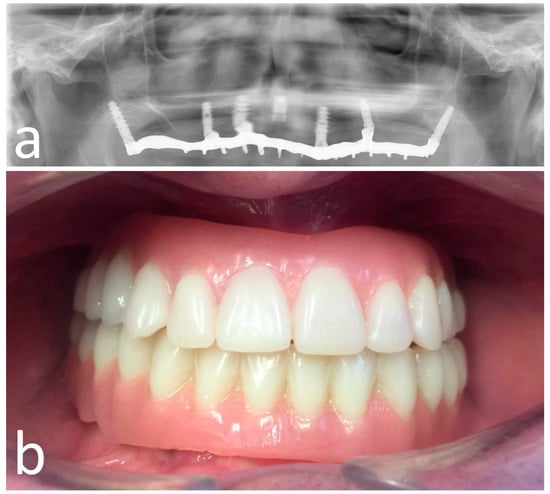

After 6 h, the provisional prosthesis was screwed, using the OT-bridge (Figure 6) or conventional M.U. abutments (Figure 7).

Figure 6.

OT-bridge abutments use the “Extragrade™” feature, a system allowing to compensate up to 80° of the divergence between two implants (a,b). Pictures c and d show the clinical (c) and X-ray (d) view of the provisional prosthesis using OT-bridge abutments.

Figure 7.

Opt X-ray (a) and clinical (b) view of the provisional prosthesis realized using conventional straight and angled multi-unit abutment (M.U.A.).